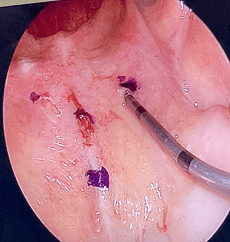

COBLATION Assisted Surgeries

A minimally invasive, low thermal technology for effective dissection and removal of tissue, COBLATION Technology has been used for ENT procedures such as tonsillectomy, turbinate reduction, laryngeal lesion debulking and soft palate.

While conventional electrosurgical devices use high temperatures to remove and cut tissue, our COBLATION Technology creates a controlled, stable plasma field to precisely remove tissue at a low relative temperature, resulting in minimal thermal damage to surrounding soft tissues. Its features include very limited depth of thermal penetration; minimal collateral tissue damage; localised effect; and controlled, volumetric tissue removal. Coblation is often preferred for its ability to reduce surgery duration and pain, minimise bleeding, and speed up recovery times in patients undergoing certain types of surgery.